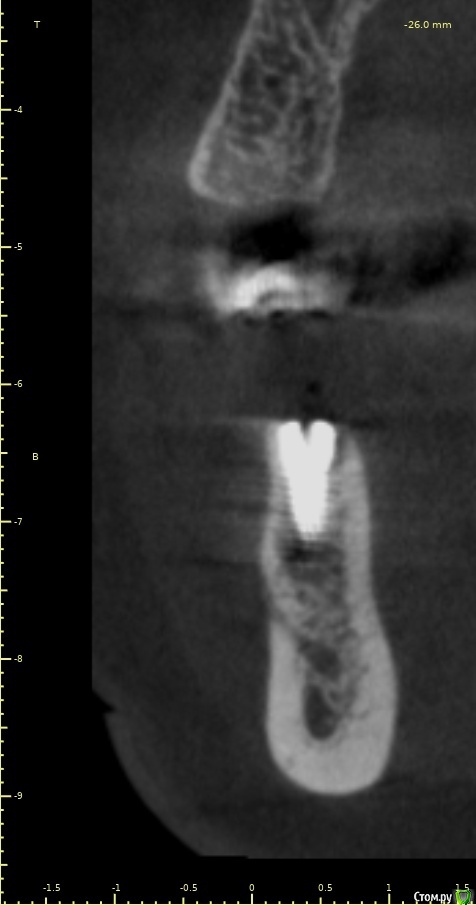

Женька Опубликовано 14 декабря, 2020 Автор Поделиться Опубликовано 14 декабря, 2020 (изменено) Наконец-то получил КТ от пациентки...Боли значительно уменьшились, практически не беспокоит... Коллеги, что думаете? Я так понимаю это уже не фон от титана? и вердикт всё-таки один? Сам склоняюсь всё-таки более к понаблюдать. Вестибулярно конечно очень тонко Толщина была ~ 6.7мм Изменено 14 декабря, 2020 пользователем Женька Ссылка на комментарий

Irouil Опубликовано 14 декабря, 2020 Поделиться Опубликовано 14 декабря, 2020 Ну и где тут язычно передавленная кортикалка? Меня смущает только картина в области верхушки симптомного винта, ну и заглубление Я бы дождался уже срока интеграции Ссылка на комментарий

Женька Опубликовано 14 декабря, 2020 Автор Поделиться Опубликовано 14 декабря, 2020 Ну и где тут язычно передавленная кортикалка? Меня смущает только картина в области верхушки симптомного винта, ну и заглублениеНе знаю, я про язычную кортику не говорил. Меня тоже смущает... и в области соседа такого фона (а это не фон я уверен) нет... А с заглублением что не так? по прицелам там 1.5-2мм, на кт почему-то этих мм вообще нет и как будто крестально стоят Ссылка на комментарий